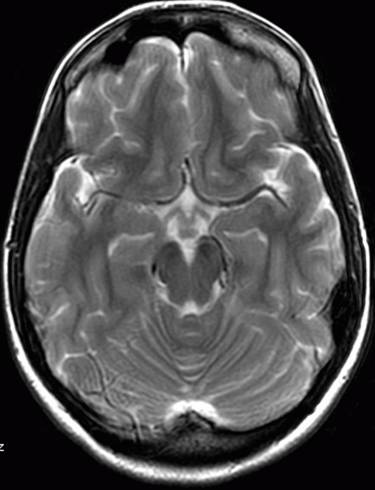

FLARI序列就是通俗所说的压水像,在这个序列中,脑灰质是高信号,也就是亮一些的,脑白质是低信号--这些类似于T2WI序列--但是在压水像上,脑脊液的信号是低的,也就是黑色的。这也是之所以称之为压水像的原因。

FLAIR 水抑制成像对脑部病理改变具有高度的敏感性,减轻水信号干扰,显示病理改变,鉴别病灶处是否为自由水,自由水为低信号。TR:9000ms TE:120ms TI:2500ms DWI:弥散加权成像,是目前能够检测活体组织内水分子扩散运动的无创性方法,是诊断脑梗塞最敏感的序列,超急性脑梗塞(小于6小时)细胞毒性水肿可明确诊断。TR:1500---2500ms TE:15---30ms

FLARI序列就是通俗所说的压水像,在这个序列中,脑灰质是高信号,也就是亮一些的,脑白质是低信号--这些类似于T2WI序列--但是在压水像上,脑脊液的信号是低的,也就是黑色的。这也是之所以称之为压水像的原因。 STIR脂肪抑制序列,在通常的T1WI和T2WI像上,脂肪都是高信号--亮的,在脂肪抑制序列--有许多种,频率抑制啊翻转恢复啊,正反相位啊--你不用明白这么许多,只要知道是压脂的序列,那么这个图像上的脂肪就是低信号--黑的。比如平时的腹部皮下脂肪,头皮下脂肪,就变成了黑色的。 一般的图像上,都会标出来FS--既是压脂序列。 DWI就是平时头部磁共振影像看起来分辨率非常差,颗粒很粗的序列,现在在临床上主要用于急性脑缺血的早期诊断,早期,脑哽塞病灶,在这个序列上是高信号的--是由于细胞毒性水肿造成扩散降低造成的。 DWI空间分辨率相对较低,靠近脑底处的磁敏感性伪影对额叶底部,颞极,小脑等处的病变评价带来影响,FLAIR不受影响。DWI上脑脊液为游离液体,其ADC类似于纯水,弥散快,在DWI上脑脊液信号明显衰减,也产生FLAIR中的黑液体效应,但二者的对比不完全相同,FLAIR除液体相为黑色外,其他组织保持T2对比。DWI的对比取决于另一组织特性参数ADC。DWI较FLAIR敏感,病变与正常组织对比更高,其异常信号范围大于常规T2和FLAIR序列。